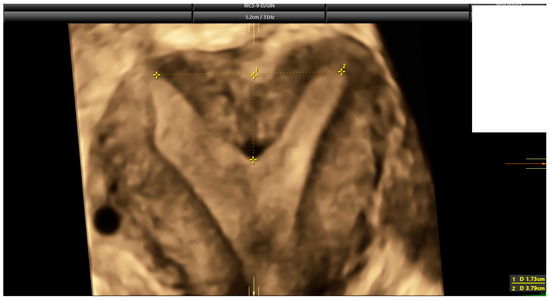

2.3. Ultrasound Evaluation

- Ludwin, A.; Martins, W.P. Correct measurements of uterine fundal internal indentation depth and angle: An important but overlooked issue for precise diagnosis of uterine anomalies. Ultrasound Obstet. Gynecol. 2021, 58, 497–499. [Google Scholar] [CrossRef] [PubMed]